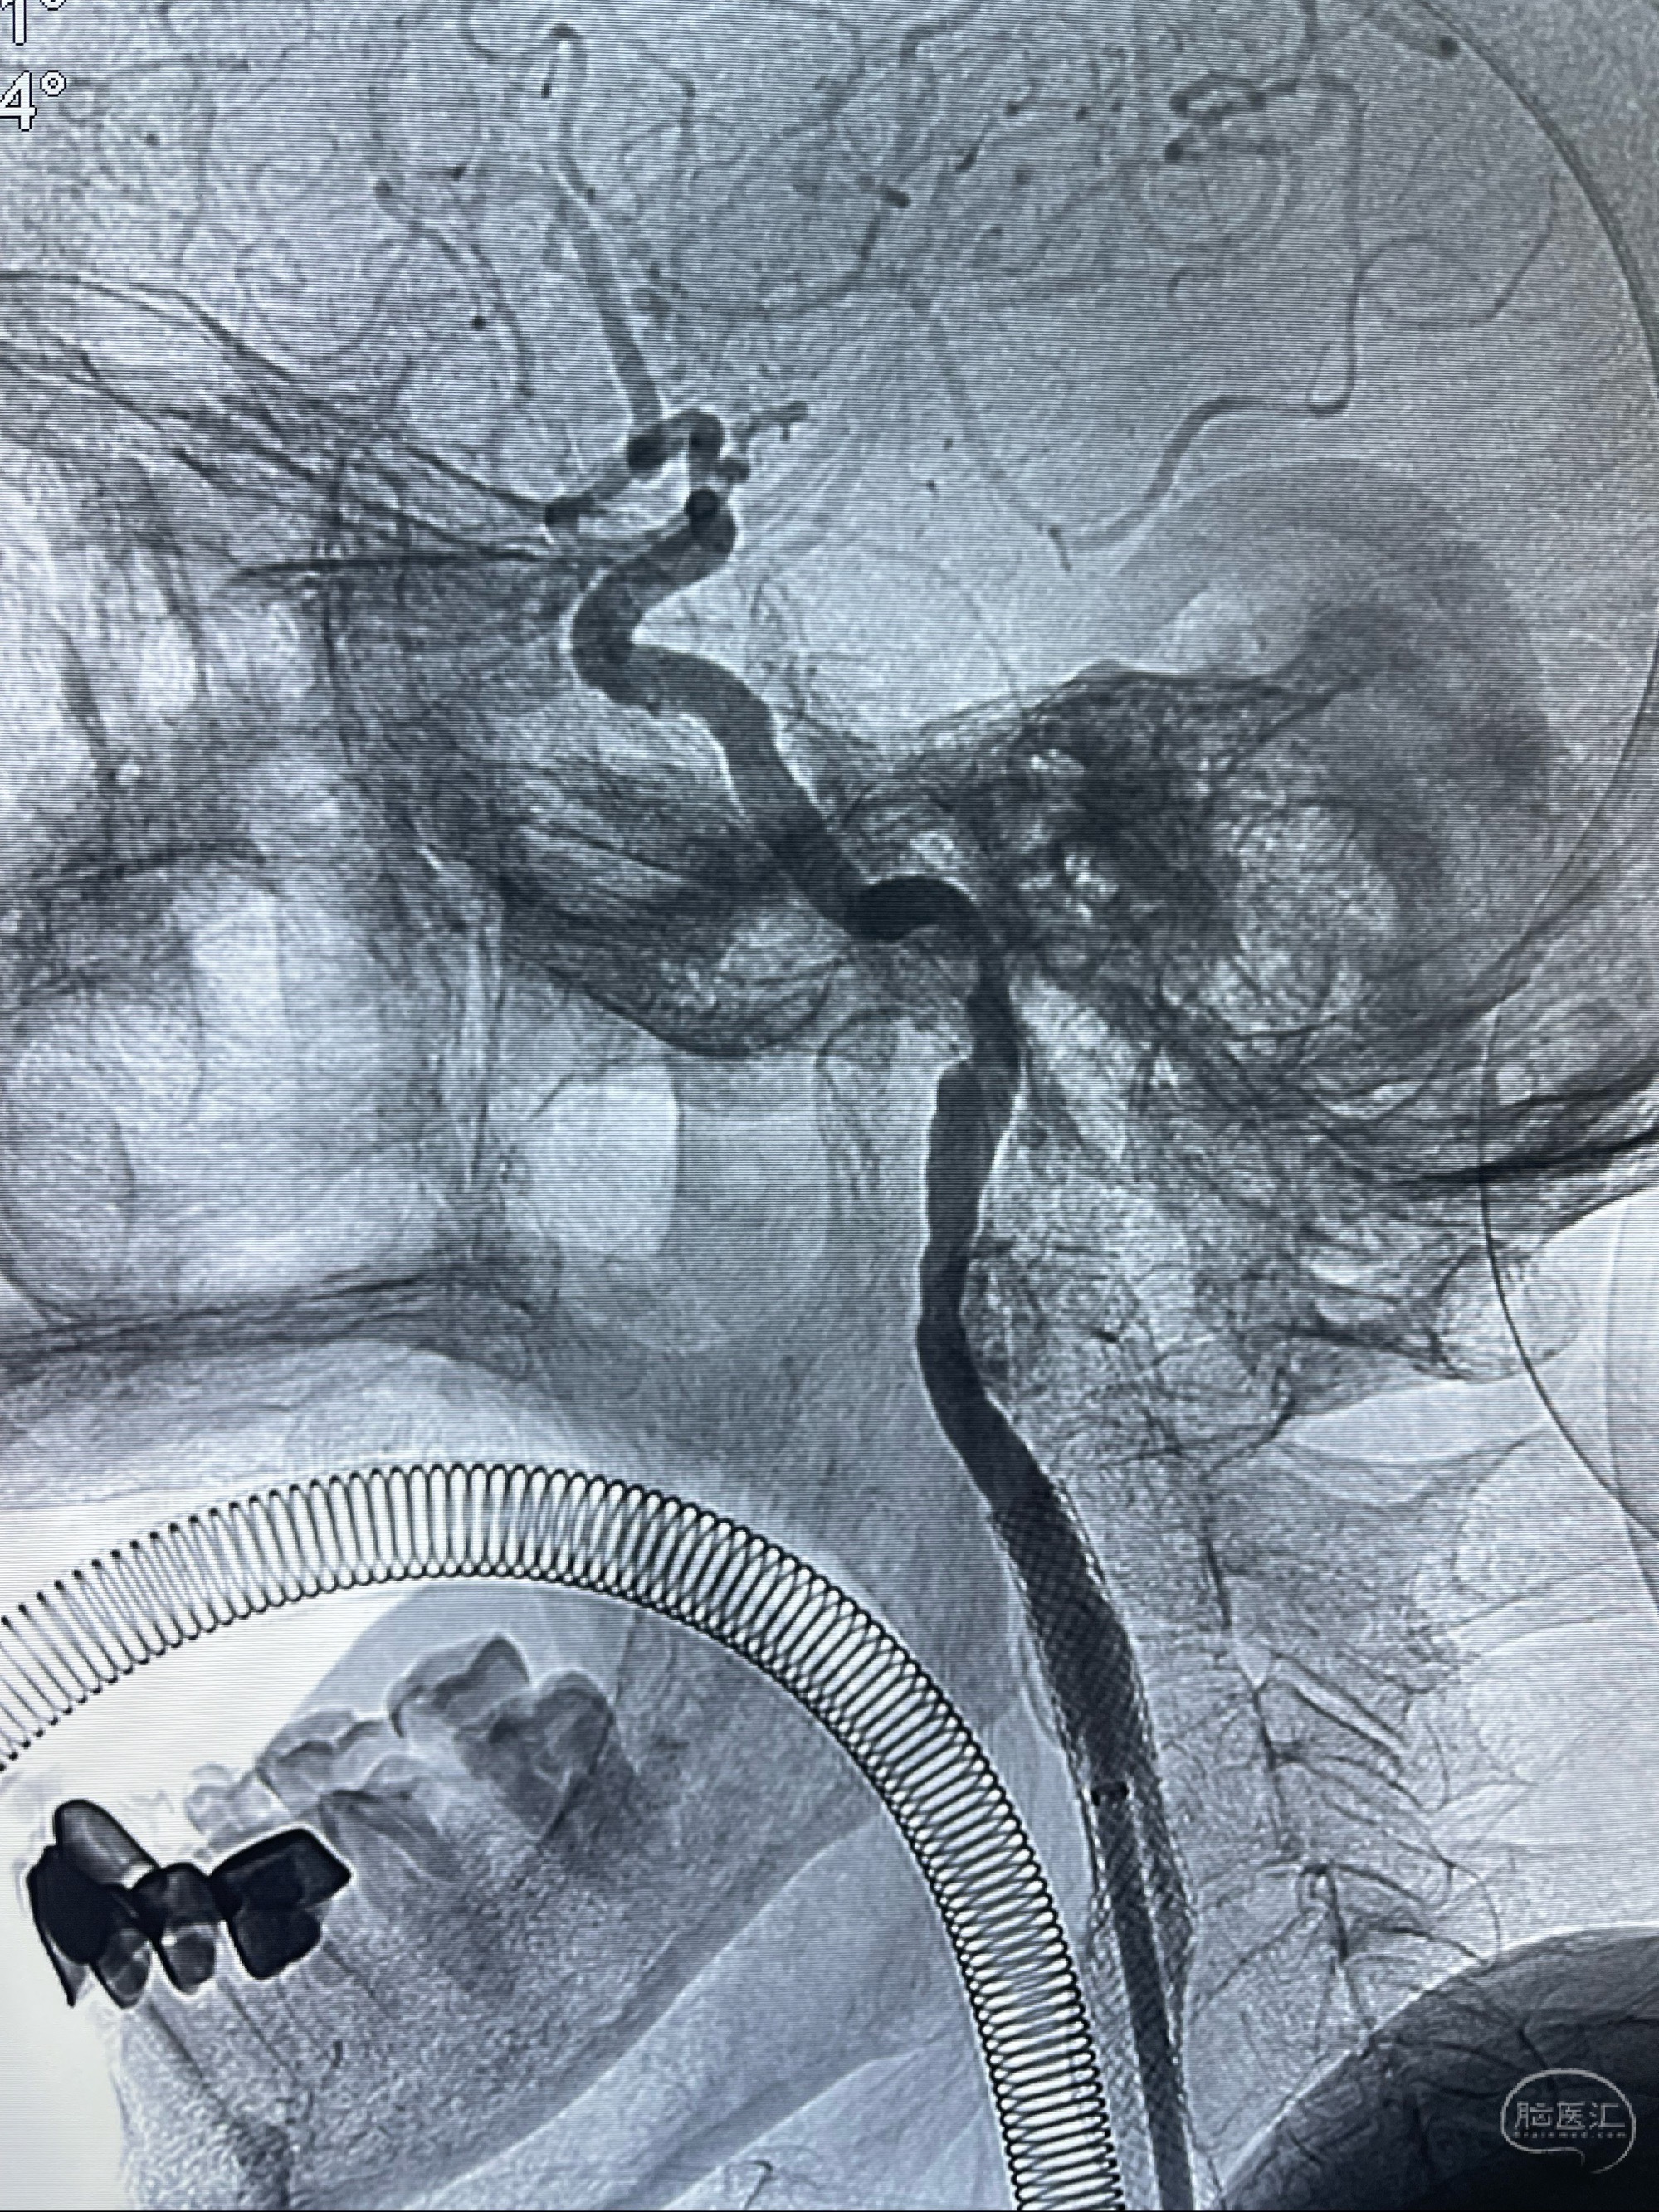

右侧椎动脉可见吻合代偿右侧颈外动脉

左侧颈总动脉起始段至分叉部闭塞,起始部呈现子弹头样改变

左侧椎动脉可见代偿显示左侧前循环

MRI:显示肿瘤侵犯右侧颈内动脉岩骨段上下,向下至原颈内动脉支架远心段,向上至颅底